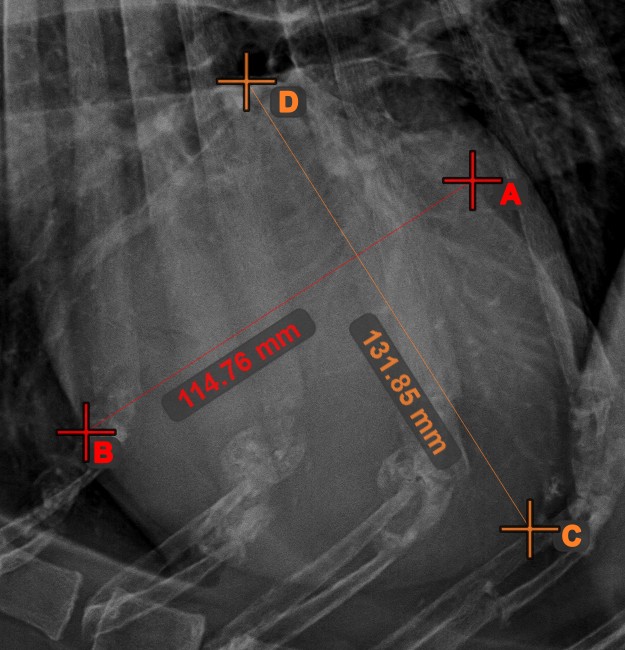

Line Measurement¶

Select the Line Measurement

tool and assign it to one of the available mouse buttons. Place the start and end points on the scene or select them from already existing points on the image. The distance between the two points will be automatically

calculated by using the default calibration data, or the recalibrated data by the length calibration measurement.

Modify the start and end point by using the Select/Move Item

tool. The distance between the two points will be automatically recalculated.